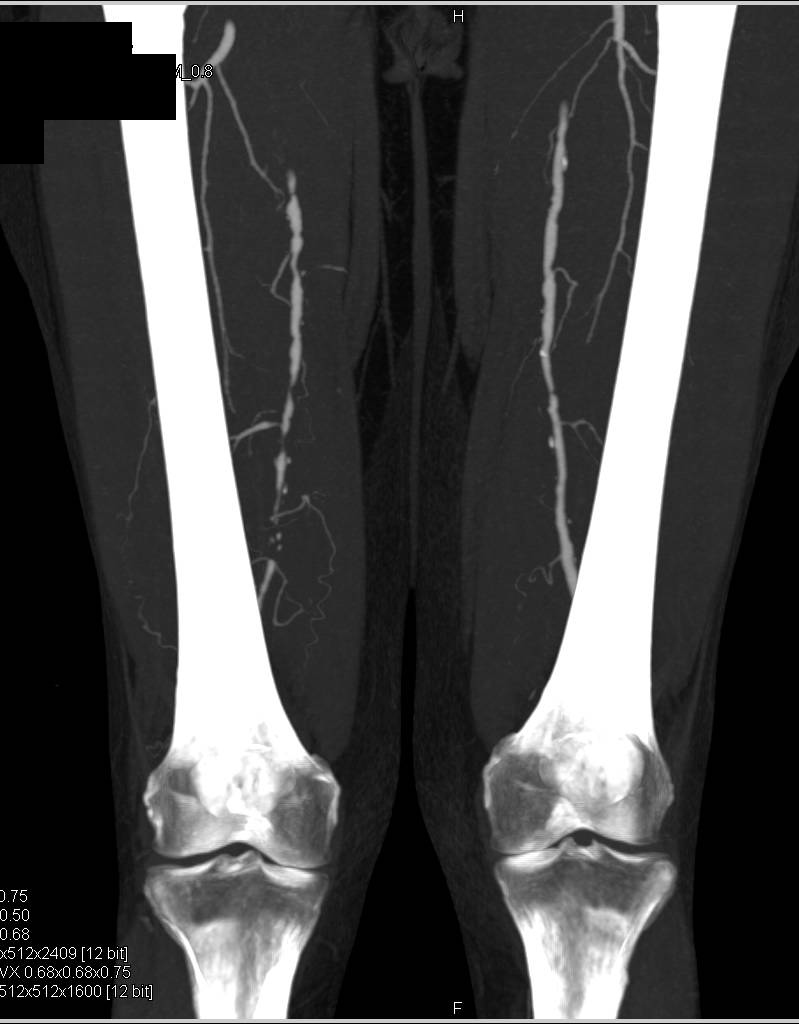

Endovascular Stent with Endoleak Seen on both Early and Late Phase Images